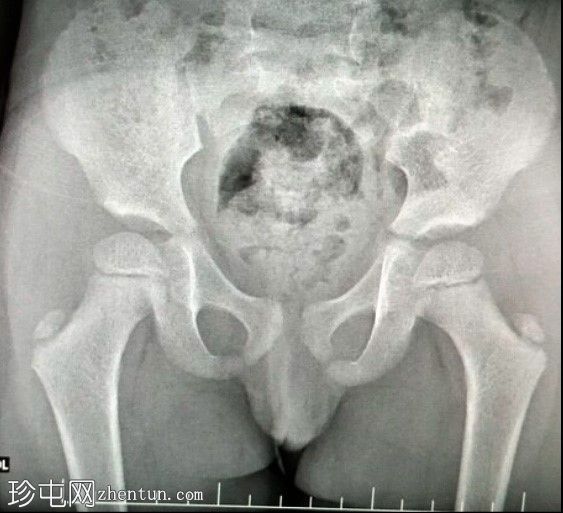

正位

初步影像显示直肠气体影正常;未见骨骼或关节异常。膀胱充盈度中等;轮廓光滑,未见小梁、囊状结构或憩室。

该生殖器造影显示膀胱与阴道之间存在共同的会阴开口,符合持续性泌尿生殖窦的诊断。